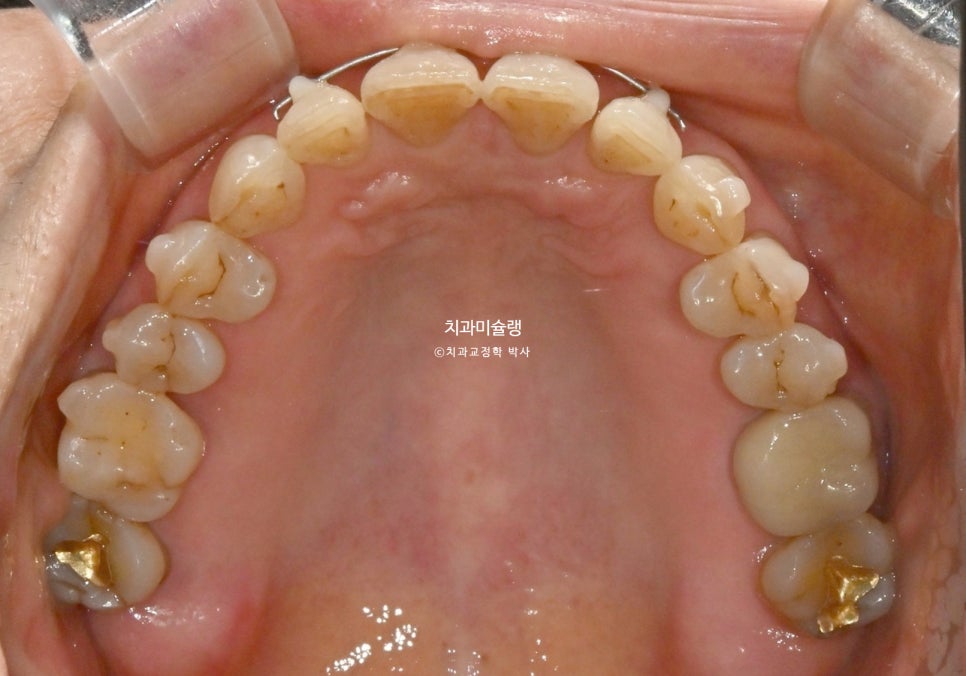

3월부터 6월까지, 7개 장치를 다 낀 후 모습입니다.

틈은 많이 줄었으나

앞니 회전이 아직 아쉽습니다.

25년 12월까지, 4개월간 7개 장치를 모두 낀 후 모습입니다.

앞니의 회전이 100% 잡히지 않아 두달간 위 앞니 4개에 MTA장치를 붙였습니다.

MTA 장치와 철사의 힘으로 앞니의 회전은 완벽히 개선되었으며 이제 소량 남은 틈을 메꿀 차례입니다.